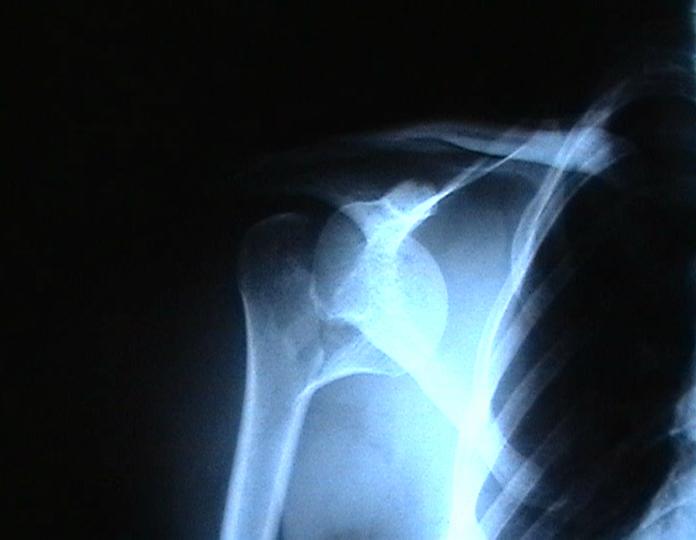

Мужчина 25 лет 16 августа 2002 г. в автоаварии получил перелом шейки плеча (снимок 1); 5 сентября в городской больнице выполнен остеосинтез пластинкой (снимок 2).К настоящему времени попал к нам на разработку ввиду выраженной контрактуры плечевого сустава. В течение последнего месяца беспокоят умеренные боли в области плечевого сустава, усиливающиеся при разработке, еще и торчит край пластинки. Нынешняя рентгенологическаякартина на снимках 3 и 4. Головка плеча уменьшается, сращение сомнительное.Кроме удаления пластинки, что еще на сегодня целесообразно сделать?Заранее спасибо.